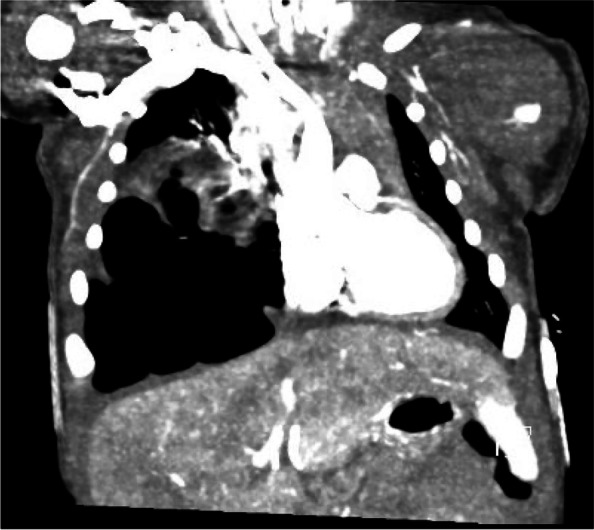

Fig. 2.

Chest computed tomography angiogram demonstrates a macrocystic multicystic lesion within the right lower lobe without systemic arterial supply

A 3.055-kg term female infant was born via Cesarean section due to failure to progress after induction of labor for gestational hypertension following an otherwise uncomplicated pregnancy. No resuscitation was required at birth and APGAR scores were 8 and 9 at 1 and 5 min, respectively. At 14 h of life, the neonate developed respiratory distress and hypoxia following breastfeeding, necessitating transfer to the neonatal intensive care unit (NICU) where she was placed on 6 L high flow nasal cannula and a maximum FiO2 of 0.26. The initial exam was significant for diminished breath sounds on the right chest, intermittent tachypnea, and bilateral mild subcostal retractions. Chest x-ray obtained on admission to the NICU was concerning for a possible congenital diaphragmatic hernia (CDH) versus multicystic mass causing a left shift (Fig. 1). An ultrasound of the lung demonstrated a right multicystic mass at the base concerning for CPAM and an intact diaphragm. The neonate was transported to a Level IV NICU for further multidisciplinary evaluation and management. Repeat chest x-ray was read as a right CDH versus CPAM filling much of the right chest with leftward mediastinal shift. Chest CT angiography demonstrated a macrocytic multicystic lesion within the right lower lobe without systemic arterial supply (Fig. 2). The pediatric surgery team was consulted, and the neonate underwent right lower lobectomy on day of life 4.